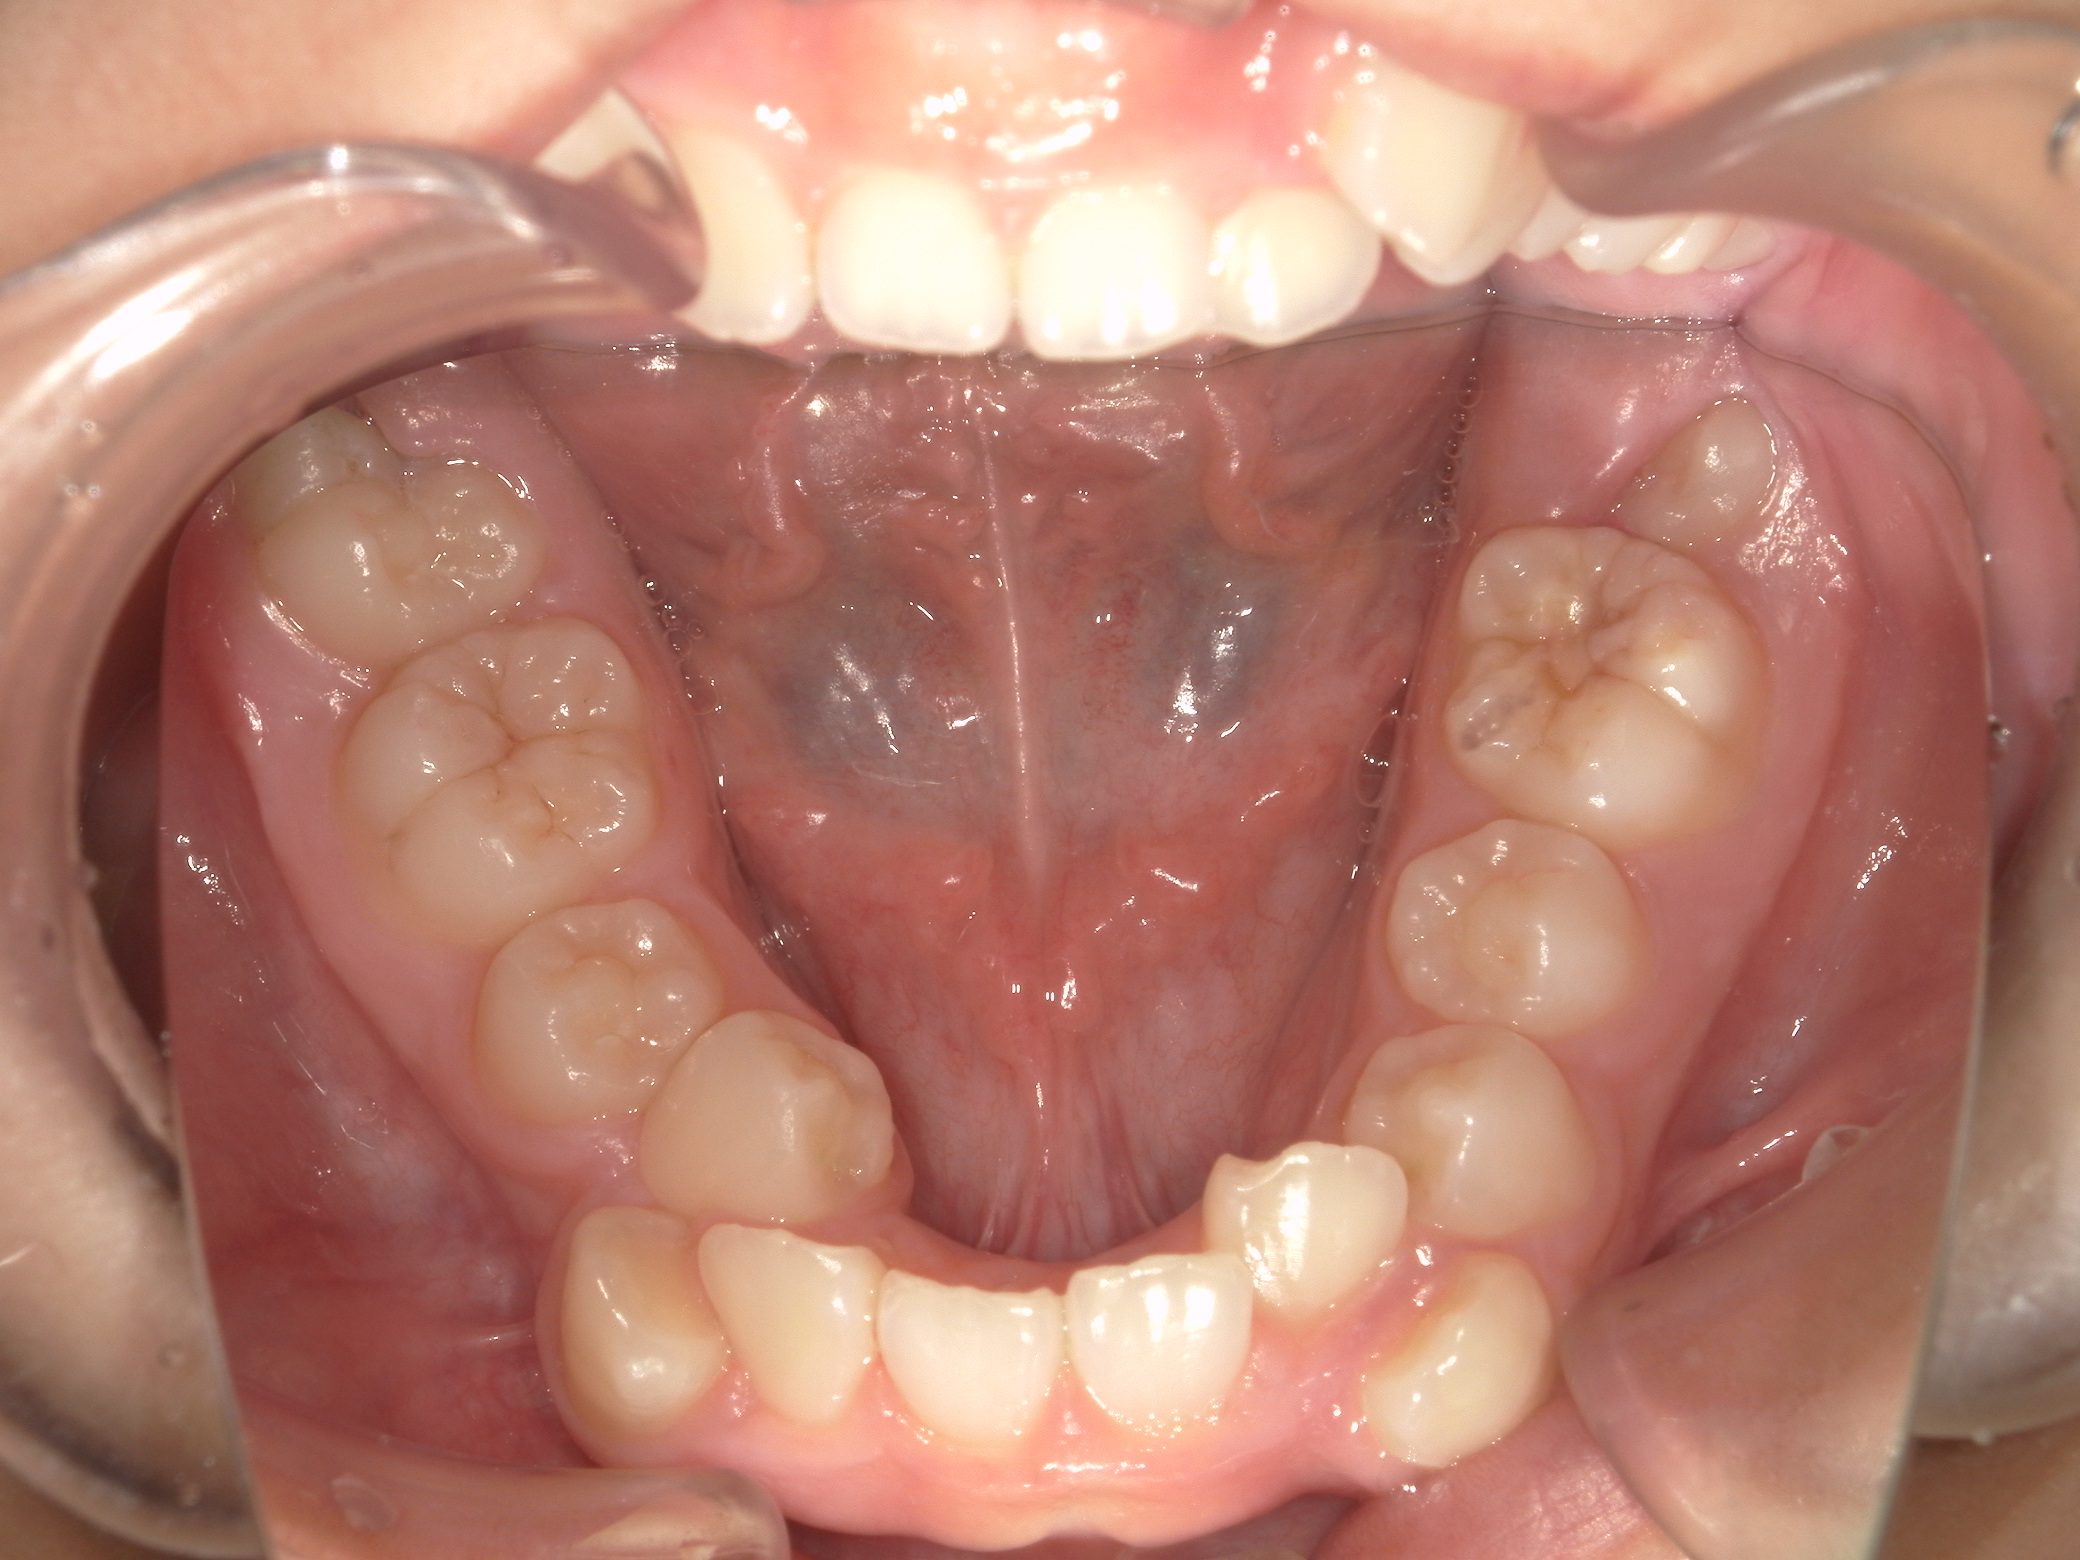

【小学生】インビザラインフル 叢生(でこぼこ)と 上顎前突(出っ歯)を改善

Before

After

八重歯と上顎前突(出っ歯傾向)が気になるということで来院

上下4本の歯を抜歯して矯正しました

しっかり装着してくれたので3年はかかると予測していましたが、1年半で終了しました

咬み合わせも改善し満足してくれました